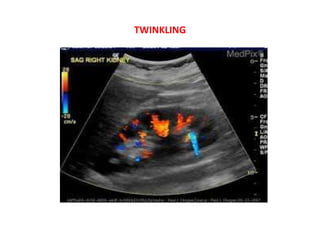

8) Twinkling artifact

Twinkling artifact is seen with (CFD) colour flow Doppler

ultrasound . It occurs as a focus of alternating colours on

Doppler signal behind a reflective object (such as a calculus),

•

It appears with or without an associated colour comet-tail

artifact

The underlying mechanism is thought to be a result of

inherent noise within the US scanner, specifically phase

(a.k.a. clock) jitter within the Doppler electronics .

Twinkling artifact is more sensitive for detection of small

stones (e.g. urolithiasis, cholelithiasis) than is acoustic

shadowing. It is most pronounced when the reflecting surface

is rough and highly dependant on machine setting

@ when the focal zone is located below a rough reflecting

surface, the twinkling artifact becomes more obvious than

when it is above it.

@ decreased pulse repetition frequency facilitates better

visualisation of the artifact.

@ The presence of renal twinkling artifact on sonography has

a high positive predictive value (78%) for the presence of

nephrolithiasis as unenhanced CT.